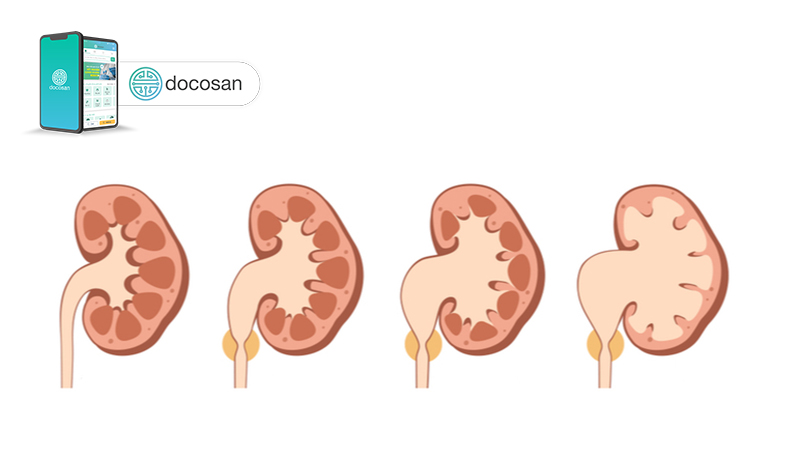

Thận ứ nước có nhiều mức độ với biểu hiện và các chữa trị khác nhau. Do đó cần có các phương tiện để xác định đúng mức độ.

Thận ứ nước có thể được chia làm 3 độ hoặc 4 độ, tùy vào hệ thống phân độ. Chính vì sự hiện diện của nhiều bảng phân độ khác nhau, có thể xảy ra hiểu nhầm khi diễn giải một độ thận ứ nước nào đó.

Tuy nhiên, bạn đừng lo lắng vì công việc diễn giải kết quả là của nhân viên y tế. Bạn chỉ cần biết rằng độ càng cao thì càng nguy hiểm (như thận ứ nước độ 3, thận ứ nước độ 4). Nhìn chung, độ 1 trong tất cả các hệ thống phân độ đều là tình trạng nhẹ, với những biểu hiện có thể không rõ ràng.